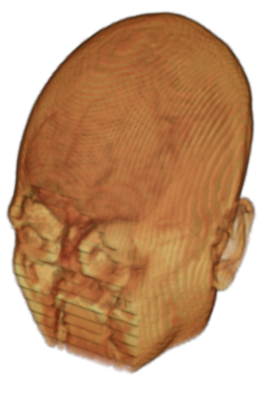

To prevent these types of attack, medical scans are currently de-identified using crude removal-based techniques [Bischoff-Grethe et al.(2007)Bischoff-Grethe, Ozyurt, Busa, Quinn, Fennema-Notestine, Clark, Morris, Bondi, Jernigan, Dale, Brown, and Fischl, Schimke et al.(2011)Schimke, Kuehler, and Hale, Milchenko and Marcus(2013)] which seek to remove privacy-sensitive parts of the head (examples in Figure 3). However, as we demonstrate, these existing techniques fail to reliably hide the patient’s identity – or they are so aggressive that they impair further medical analyses. A better solution is needed.

A handful of de-identification techniques exist for MRI scans, which are conventionally used for sharing and distribution of MRI data. These existing methods rely on a removal approach to privacy. DEFACE [Bischoff-Grethe et al.(2007)Bischoff-Grethe, Ozyurt, Busa, Quinn, Fennema-Notestine, Clark, Morris, Bondi, Jernigan, Dale, Brown, and Fischl] estimates the probabilities of voxels belonging to the face based on an atlas of healthy control subjects. The scan is de-identified by setting intensities of voxels whose probabilities are small enough to zero. QUICKSHEAR [Schimke et al.(2011)Schimke, Kuehler, and Hale] is a fast but simple approach that computes a hyperplane to divide the MRI into two regions: one containing facial structures, and the other containing the brain of the scan. Voxels in the first part are set to zero. FACE MASK [Milchenko and Marcus(2013)] uses a filtering method to blur the facial features. These existing de-identification approaches are based on traditional computer vision techniques; we believe that the proposed algorithm is the first to adopt a learning-based approach.

Benchmark De-Identification Methods. We compare our result with three publicly available and widely-established methods for de-identification of MRI head scans, depicted in Figure 3. All methods have in common that they (1) are not deep-learning-driven, (2) require no additional training and (3), are used on a day-to-day basis in neuroscience and clinical research. All procedures were applied with default settings on images of resolution . The methods include QUICKSHEAR [Schimke et al.(2011)Schimke, Kuehler, and Hale], FACE MASK [Milchenko and Marcus(2013)], and DEFACE [Bischoff-Grethe et al.(2007)Bischoff-Grethe, Ozyurt, Busa, Quinn, Fennema-Notestine, Clark, Morris, Bondi, Jernigan, Dale, Brown, and Fischl]. Descriptions of the methods are provided in the Appendix. We also include MRI WATERSHED [Ségonne et al.(2004)Ségonne, Dale, Busa, Glessner, Salat, Hahn, and Fischl], a skull-stripping method that removes everything except the brain.